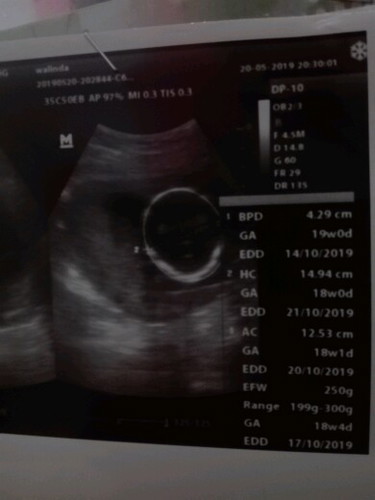

hasil usg

Bun boleh ngga sih tanya lagi . Kok td aku baca² komen soal USG . Jd ceritanya itu aku terakhir USG itu bulan mei tgl 20 Mei hasil USG menunjukkan usia kandungan 18week Nah bulan ini aku USG lagi, kali ini aku USG di dokter yg berbeda. Ditanggal 25 Juni . Hasil USG usia kandungan aku menunjukkan 21week Ada yg aneh ngga sih Bun ? Apa iya babyku ngga berkembang ?

patokan hpl dan usia kehamilan selain dr HPHT, bisa diambil dr usg TM 1 bun (7-11 minggu) klo setelahnya sdh tdk akurat u/ menentukan uk dan hpl nah.. jika di TM selanjutnya usia kehamilannya mundur, kemungkinan memang perkembangan janinnya terhambat (ga sesuai usia kehamilan), tp sebaiknya pembandingnya di dokter dan alat usg yg sama coba dikonsultasikan dg DSOGnya bun,

Kalo 20 mei 18w. Sekarang harusnya 22w lebih ya bund. Tapi bukan karena tidak berkembang, tapi mungkin ukuran janin lebih kecil dari yang seharusnya karena usg kan dihitung dari berat dan panjang janin. Kalo masih selisih beberapa hari gapapa bund.

Klo sy itung umur janinnya berdasatkan HPHT ja bun, trus saat mau usg kn dokter jg biasanya tanya kapan HPTP nya n hasil usg nya jg paling cm selisih bbrpa hr ja.. Moga debay sm bunda sehat" ja slalu.. Aamiin

Ya beda-beda atuh bun ga perlu khawatir. Kan USG mah lihatnya dari besar janinnya. Jadi wajar beda-beda. Yang penting hitung usia kandungannya dari hpht aja.